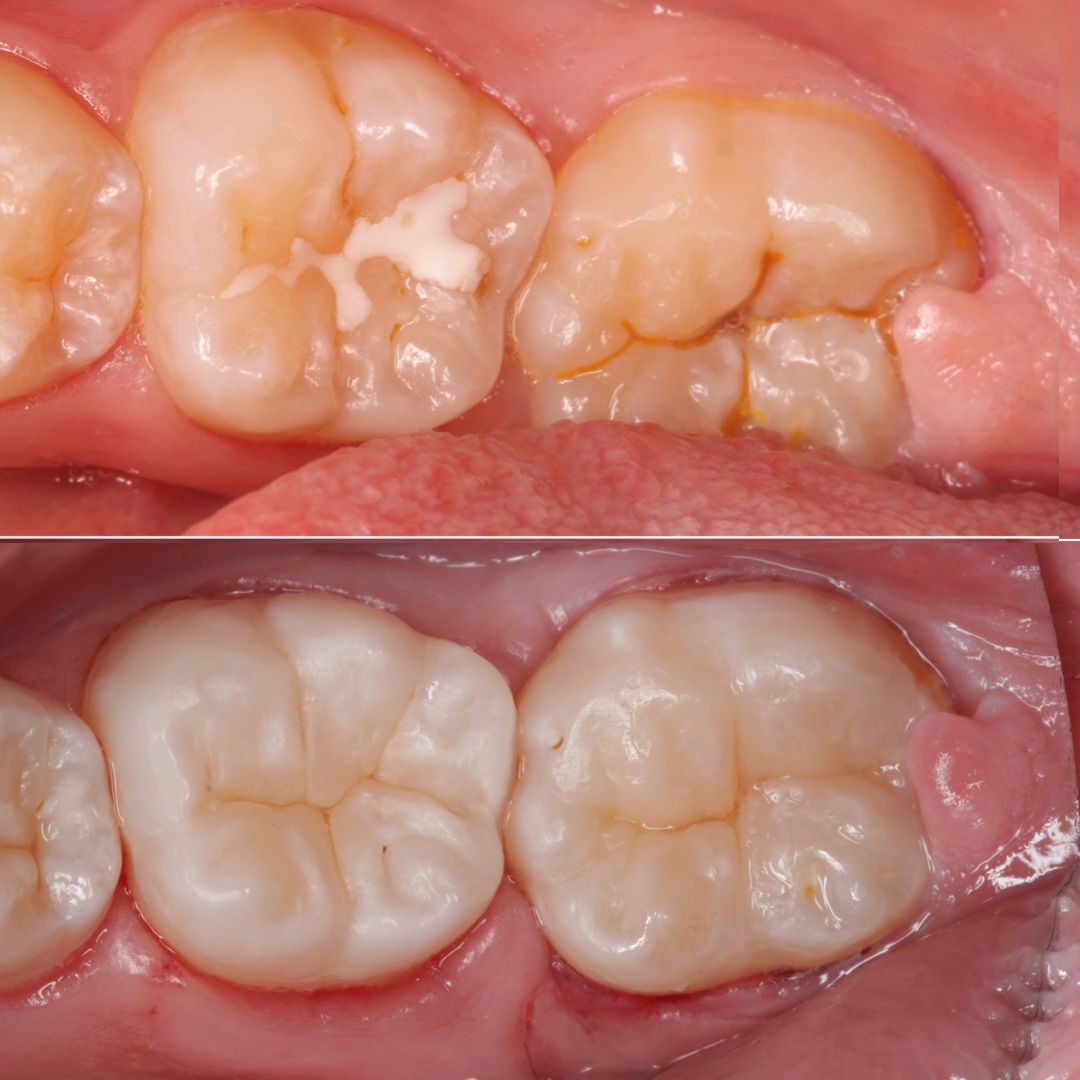

Dr Valeriia w 2015 ukończyła Uniwersytet Medyczny na kierunku Stomatologia w Charkowie, od kilku lat mieszka w Polsce, a posługując się płynnym językiem polskim, ukraińskim, rosyjskim i angielskim oraz prezentując światową jakość swojej pracy bardzo szybko zdobyła zaufanie i sympatię pacjentów. Doświadczony endodonta - większość kierowanych do niej przypadków zębów skazanych na usunięcie jest w stanie uratować leczeniem kanałowym. Znana z wybitnie estetycznych i biomimetycznych wypełnień kompozytowych. Jej prace to przykład doskonałej odbudowy zęba, zarówno pod kątem funkcjonalnym jak i estetycznym.

Pracuje zawsze pod mikroskopem, w osłonie koferdamu i zawsze w oparciu o tomografię komputerową, w klinice posiada najnowocześniejszy sprzęt tomograficzny oraz narzędzia maszynowe do leczeń kanałowych.

Jej pasją jest leczenie zachowawcze, wypełnienia z jej ręki są małymi dziełami sztuki, idealnie i anatomicznie wykończonymi. Precyzja i cierpliwość w sposobie pracy w połączeniu z wysokim poczuciem estetyki umożliwiły tej naturalny rozwój w kierunku stomatologii estetycznej. Dr Valeriia wykonuje precyzyjne kompozytowe odbudowy zębów przednich, bondingi oraz prace „z ręki”.

Doktor uważa, że obraz mówi więcej niż słowa, zapraszamy do zapoznania się z galerią jej prac.